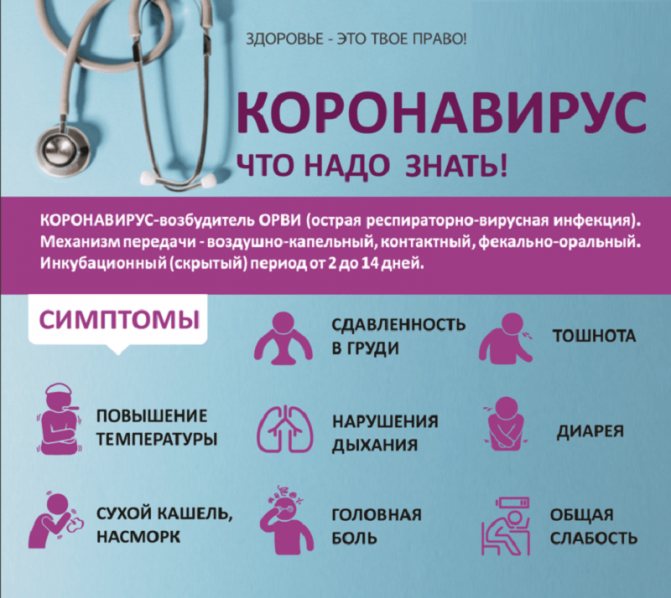

Наиболее очевидные признаки того, что уже переболел

За время наблюдения за больными медики накопили немалый опыт, позволяющий узнать, что человек уже переболел коронавирусом. Вот в каких случаях можно заподозрить у себя COVID-19:

- вы заболели, но симптомы были гораздо более выраженными, чем при стандартных случаях простуды или гриппа;

- вы отметили, что во время болезни у вас пропадало обоняние, привычный вкус еды тоже менялся;

- после выздоровления сохранилась одышка — наиболее явный и распространенный симптом коронавирусной инфекции;

- на протяжении долгого времени у вас был сухой кашель, причиной которого не могли быть загрязненный воздух или аллергия;

- на протяжении месяца или двух сохранялись слабость и усталость.

Одно из наиболее длительных последствий коронавирусной инфекции — ощущение усталости и слабости. Если при гриппе они сохраняются не больше недели или двух, то в тяжелом случае больные испытывают эти симптомы до 2 месяцев.

Другие признаки, которые отмечают специалисты: кожная сыпь, аритмия даже в состоянии покоя. Также могут возникать и другие необъяснимые явления, с которыми человек не сталкивался до этого. COVID-19 может быть и кишечного типа. В этом случае человека беспокоят боли в животе и диарея.